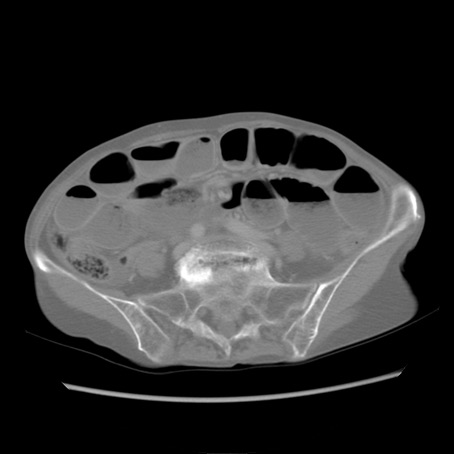

冠状断像